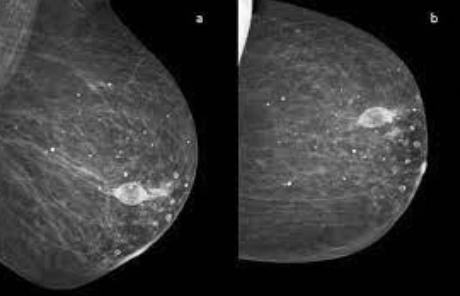

20

Q

Dx

A

Necrosis grasa